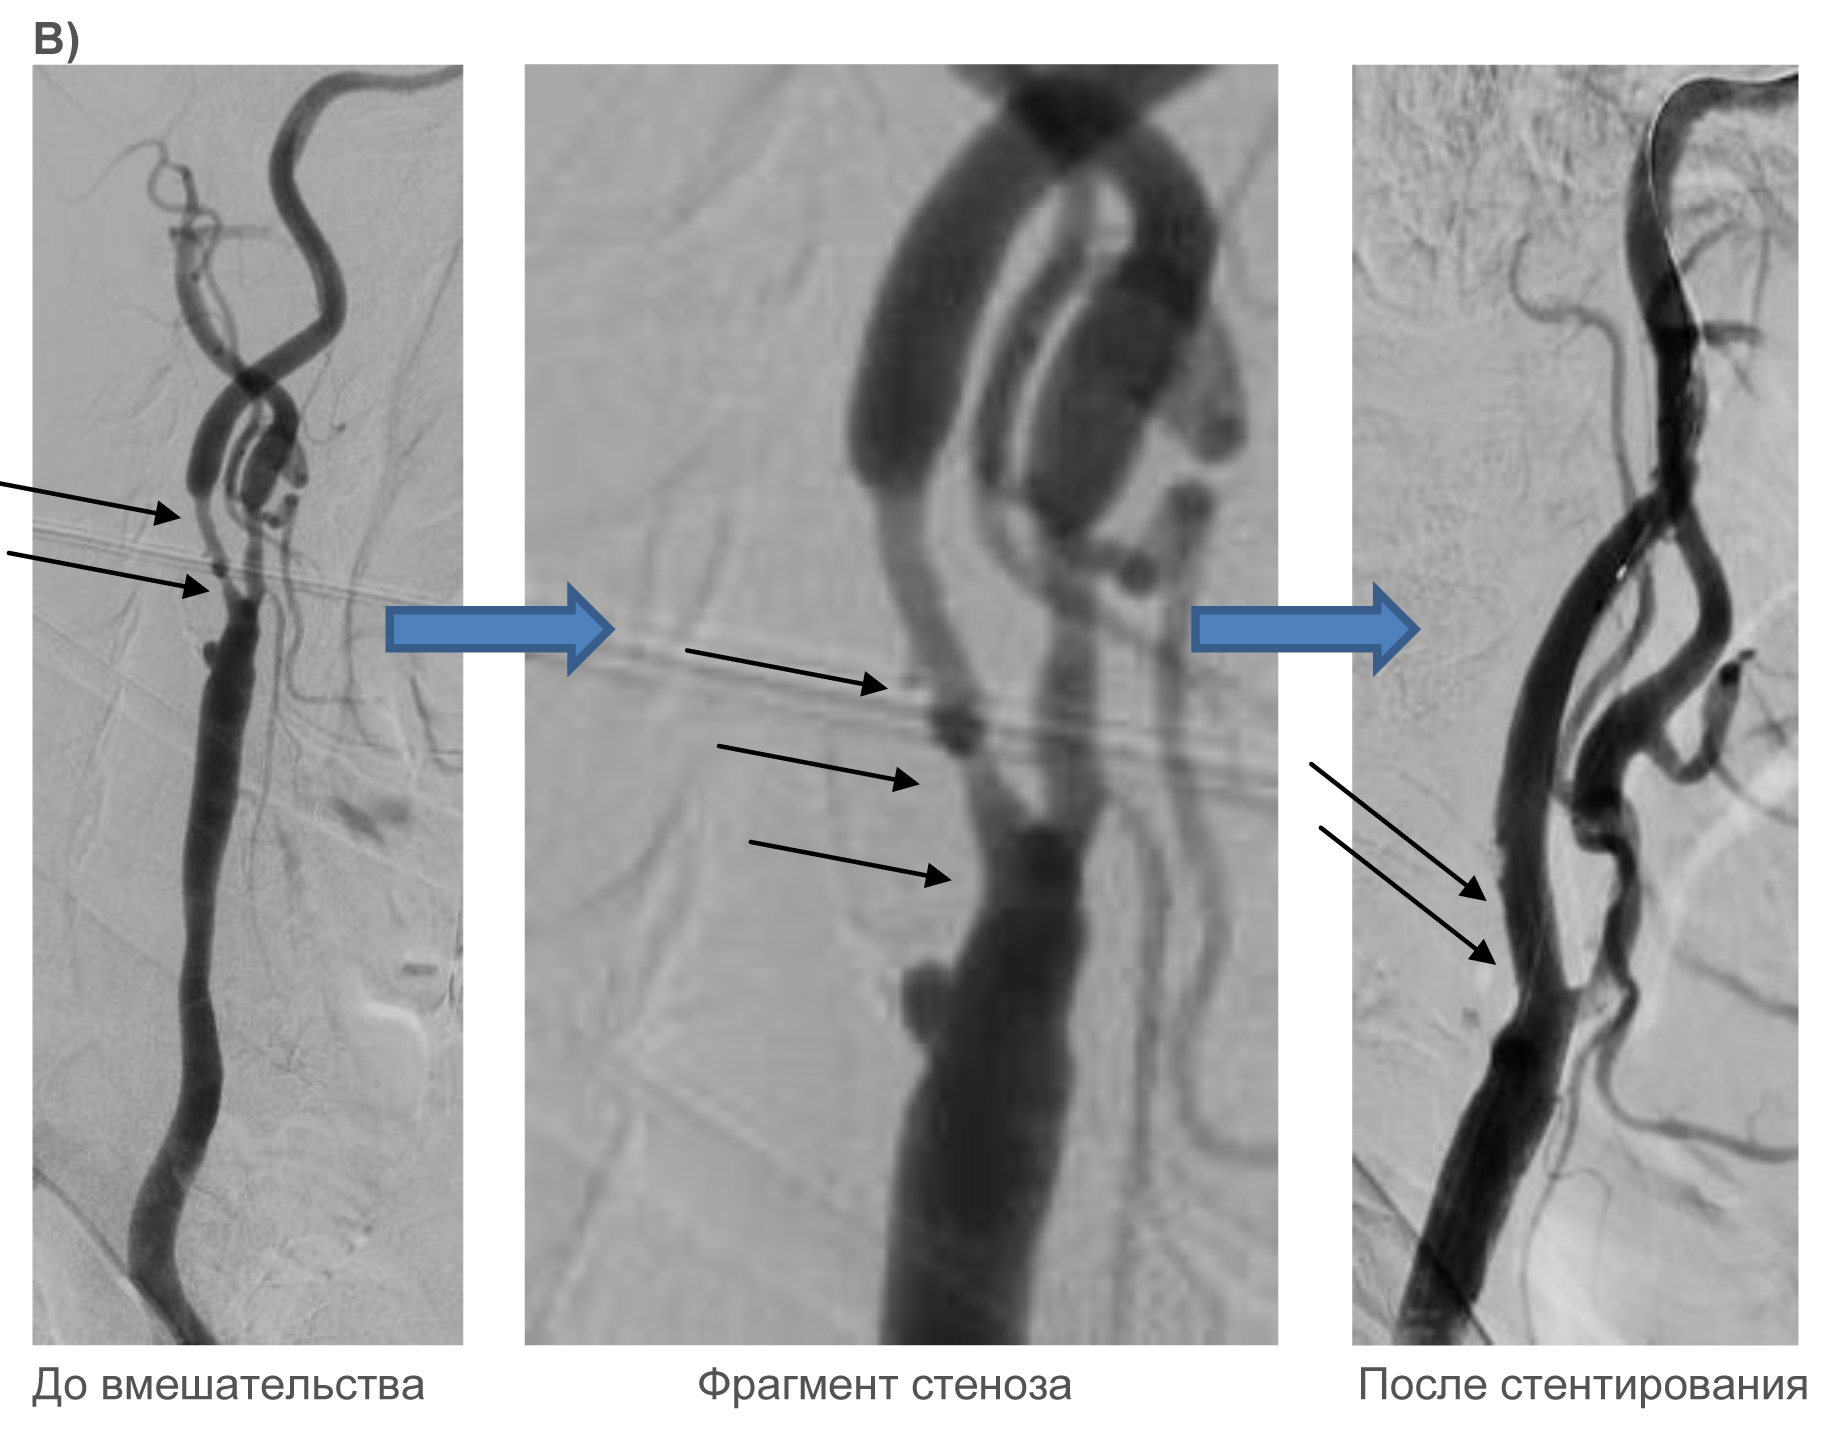

Клинические примеры:

Для иллюстрации клинических примеров выполненных стентирований сонных артерий отсутствует необходимость подробного описания состояния пациентов до и после проведенного вмешательства, т.к. самочувствие пациента может значимо не меняться. Основной целью вмешательства является профилактика инсульта.

Ниже – несколько наглядных примеров выполнения стентирования: